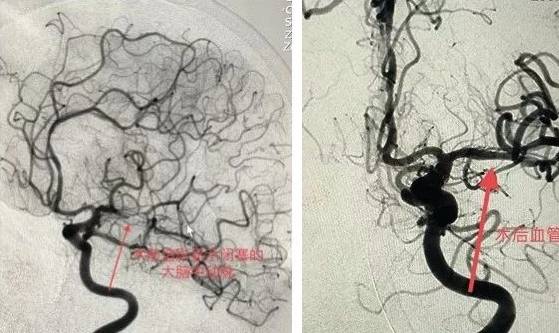

入院第二天,李老太病情加重,急查腦CT血管顯示「左側大腦中動脈嚴重狹窄」,醫生立即商議,進行手術。